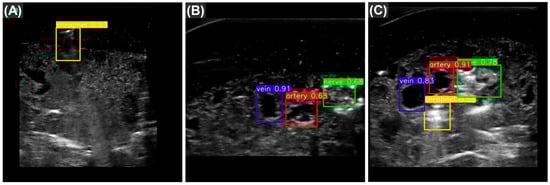

| Category | Count | Recall | Precision | AP:0.50 |

|---|---|---|---|---|

| Vein | 1080 | 0.955 | 0.963 | 0.981 |

| Artery | 1115 | 0.981 | 0.985 | 0.993 |

| Nerve | 1113 | 0.954 | 0.949 | 0.937 |

| Shrapnel | 1378 | 0.819 | 0.819 | 0.858 |